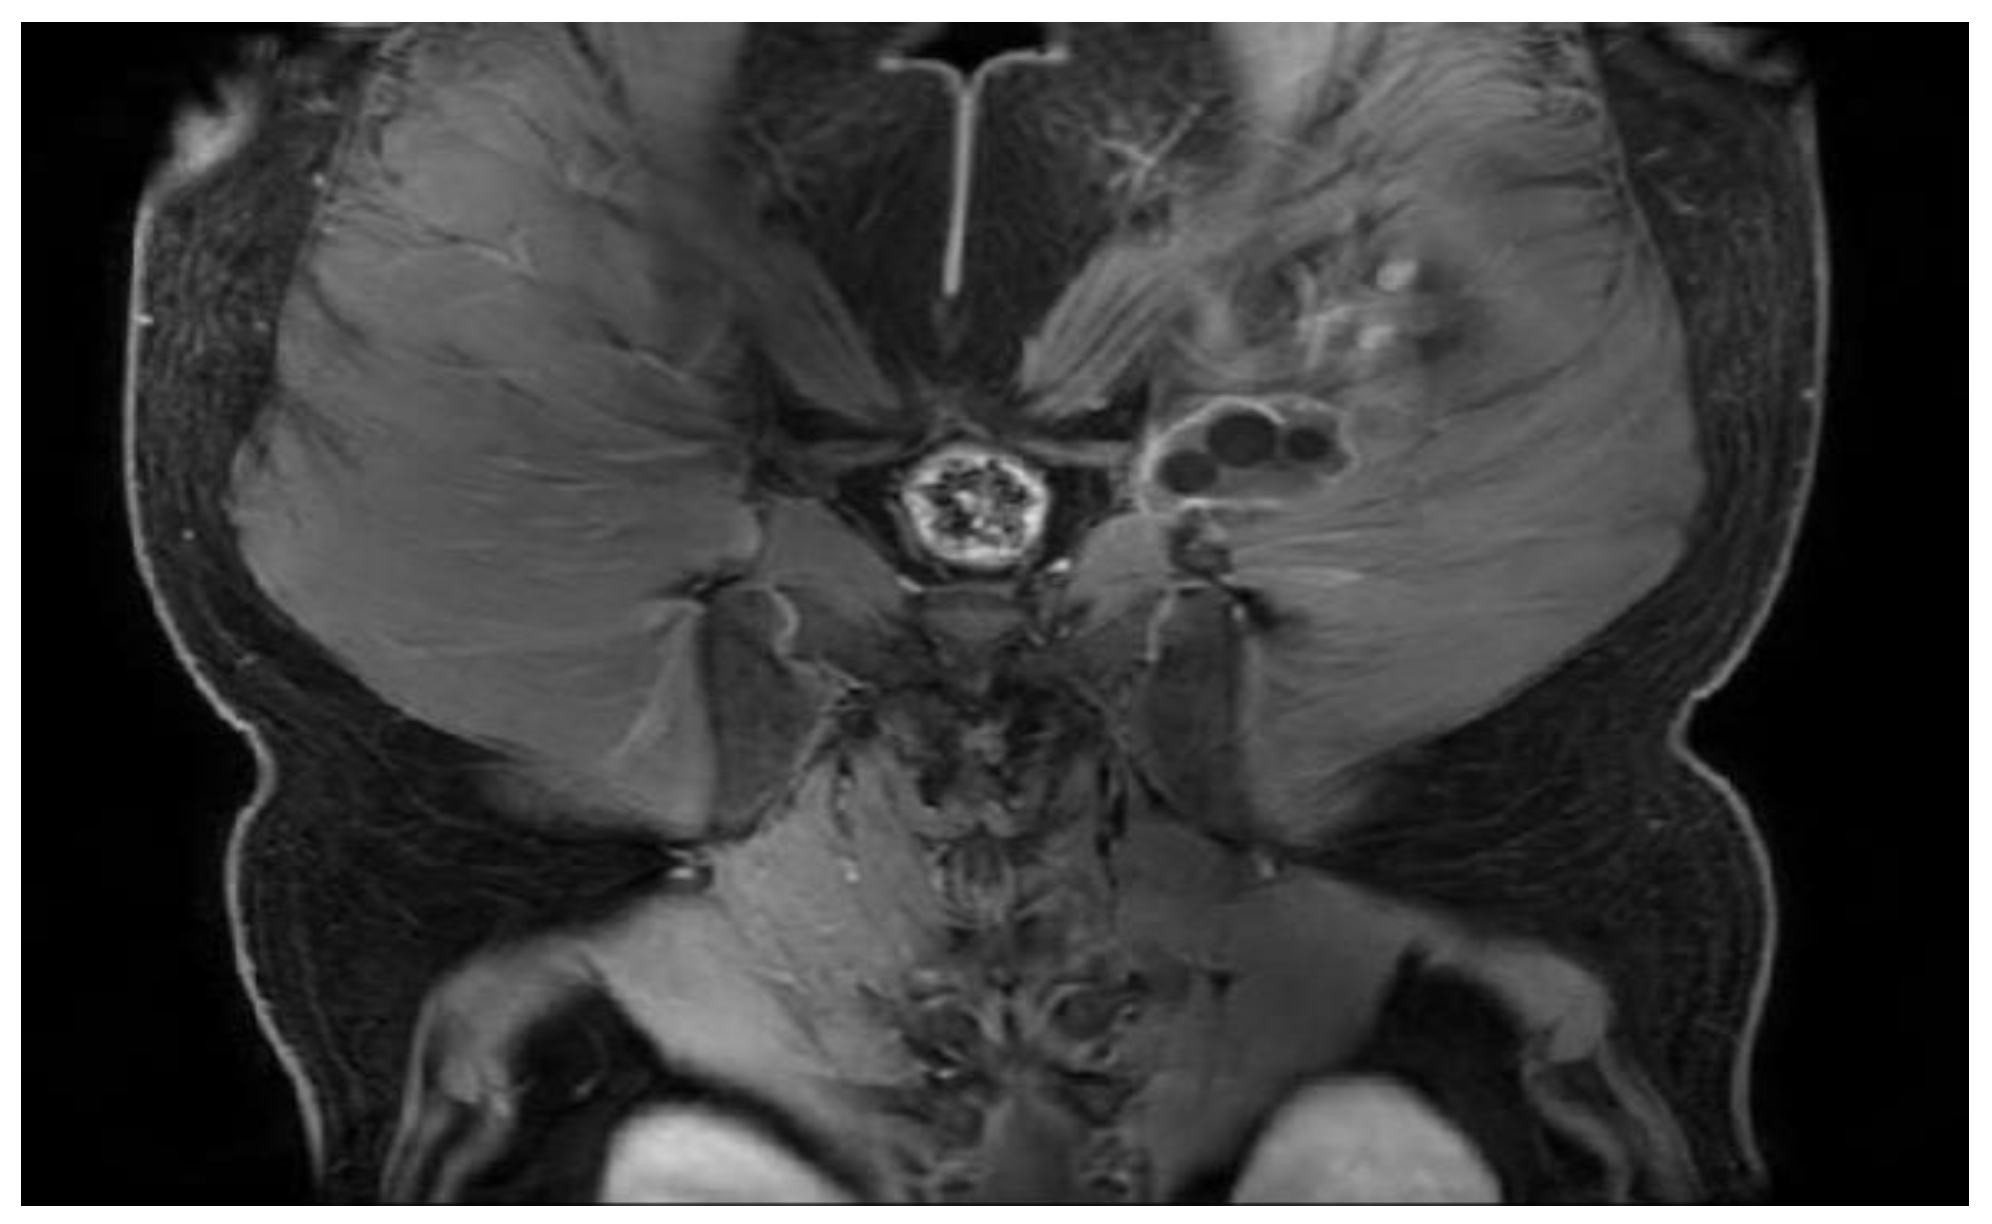

Figure 21.

T1W +C MRI sequence, coronal—Outstanding hydatid cyst with daughter cells present, located deep to the gluteus maximus muscle on the left side, with peripheral gadolinophilia.